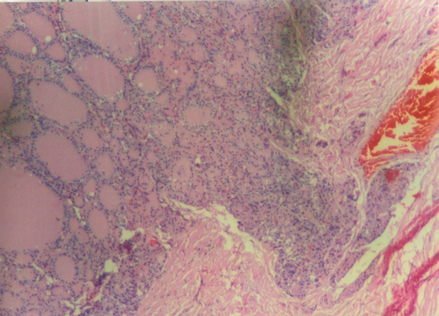

Carcinoma of the thyroid has been classified in this main histological types, papillary carcinoma, follicular carcinoma, medullary thyroid carcinoma and anaplastic carcinoma. Papillary carcinoma type. It is the more frequentlyseen in adults. We have find only one case of this type that presents acharacteristicnodule with papillary pattern (Figure 1). The aspect of nuclei of epithelial cells in no papillary areas are also atypical,looks more like those of the papillary area. Also there is a case with tall epithelial cells,that also have been related to papillary carcinoma (Figure 2).

Figure 1 Papillary nodule is seen. Appreciate that cells in no papillary areas, are different from cells of normal follicles.